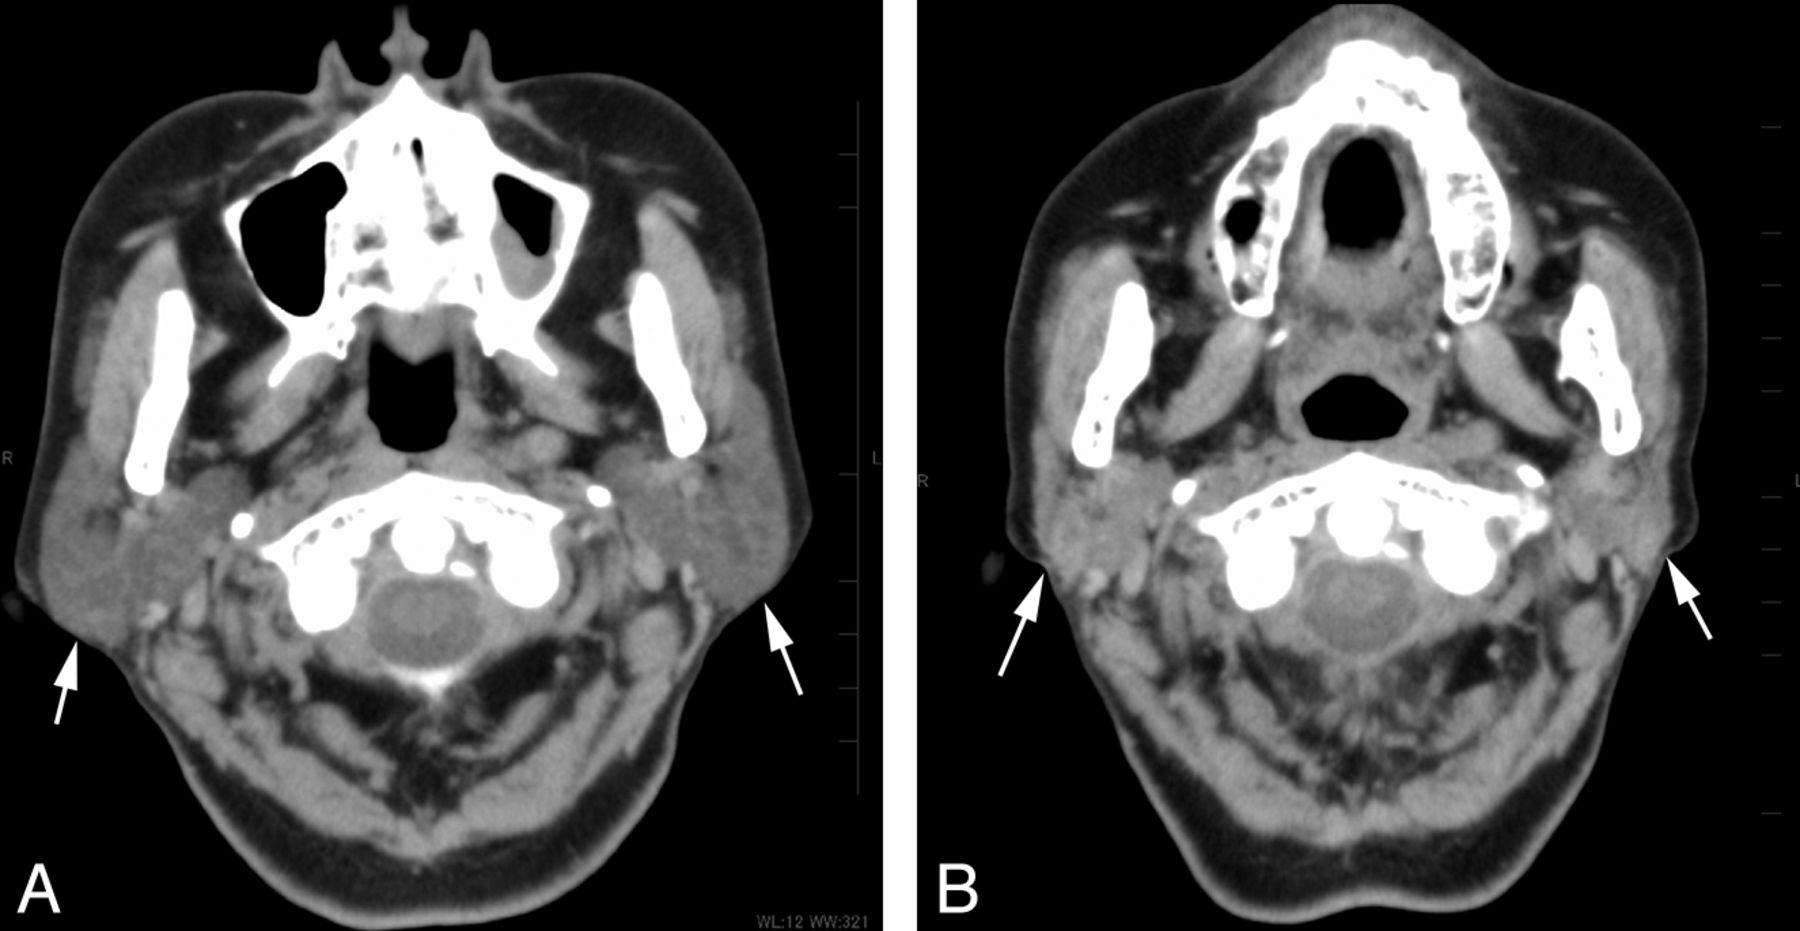

The reduction volume (mean ± SD, 95% confidence interval) in the submandibular gland after RIT, depending on the grade of scintigraphy, was 4.0 ± 3.1% (2.0%–6.1%) for grade 1 (n = 11); 14.7 ± 9.2% (10.8%–18.5%) for grades 2 and 3 (n = 24); and 42.3 ± 11.3% (28.3%–56.3%) for grade 4 (n = 5) (Figs 4 and 5). The submandibular gland volume after the treatment significantly decreased with an increase in the grade of dysfunction on scintigraphy (P < .001, 1-way analysis of variance). There was a significant difference in the reduction volume between grade 1 and grades 2 and 3 (P < .001), grades 2 and 3 and grade 4 (P < .001), and grade 1 and grade 4 (P < .001) groups, as determined by the Tukey Honestly Significant Difference test (Fig 3).

A 68-year-old woman who underwent 4 radioiodine treatments shows severe dysfunction of the submandibular gland on scintigraphy. Non-contrast-enhanced CT images (A) before and (B) after the treatment. The bilateral submandibular glands (arrows) show a prominent volume reduction of 56% but a minimal increase in attenuation of 14 HU on CT after the treatment.

The attenuation change (mean ± SD, 95% confidence interval) in the submandibular gland after RIT, depending on the grade of scintigraphy, was 4.4 ± 3.5 HU (2.0–6.7 HU) for grade 1 (n = 11); 5.3 ± 5.9 HU (2.8–7.8 HU) for grades 2 and 3 (n = 24); and 10.2 ± 2.8 HU (6.8–13.7 HU) for grade 4 (n = 5) (Figs 4 and 5). In the submandibular glands, there was no significant correlation between the attenuation change and the grade of dysfunction on scintigraphy. No significant differences were noted among the attenuation changes for each group (Fig 6).

CT examinations of the head and neck are commonly performed during the follow-up period after RIT to screen for recurrence and metastasis. Because iodine contrast material is contraindicated for a few weeks before the RIT, we obtained noncontrast CT images. Our current results suggested that the volume change of the salivary gland measured on CT could be an indicator for the assessment of salivary dysfunction after RIT. A volume reduction of nearly 20% in the parotid and 30% in the submandibular gland suggested severe dysfunction of the gland, with sensitivities of 86% and 100% and specificities of 100% and 97%, respectively. A few authors have reported radiation-induced volume loss in the salivary glands in patients receiving external radiation,10⇓⇓–13 and Teshima et al10 suggested a correlation between the loss of gland volume and decreased saliva production. However, no previous reports have investigated the relationship between the changes in the volume of the salivary gland on CT and the grade of salivary gland dysfunction in patients who undergo RIT.

The increase in attenuation after RIT on non-contrast-enhanced CT was also significantly correlated with gland dysfunction on scintigraphy in the parotid glands. An attenuation increase of nearly 10 HU indicated severe dysfunction of the gland, with a sensitivity of 81% and a specificity of 95%. Such a correlation was not present in the submandibular glands, possibly because of the high attenuation already present in the glands before treatment.17 In the current study, the pretreatment attenuation of the submandibular gland was significantly higher than that in the parotid gland. Moreover, its attenuation before treatment showed an inverse correlation with the attenuation change in the parotid gland, while that in the submandibular gland did not show such a correlation. Salivary dysfunction occasionally becomes more evident during a period of several months to 1 year after the last RIT, indicating that slowly progressing fibrosis is part of the pathologic process involved in radiation-induced sialoadenitis.2,8 We think that replacement of the fat tissue by fibrosis within the salivary gland contributes to its attenuation increase after RIT.